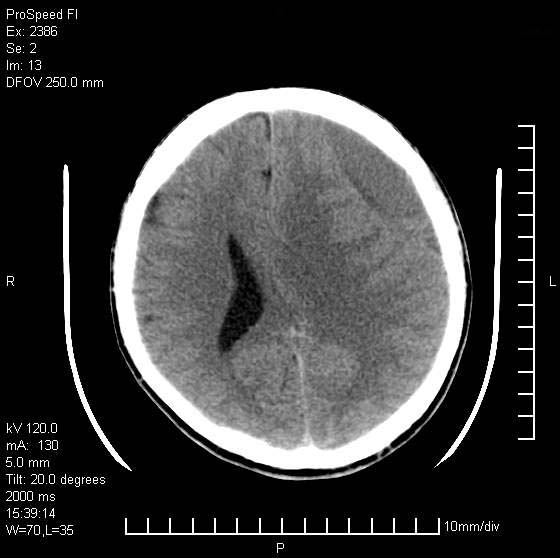

以下是引用天南地北在2007-9-19 18:43:00的发言:[br]典型慢性硬膜外血肿[br][br][本贴已被 天南地北 于 2007-9-19 18:44:11 修改过]

以下是引用曼一拍在2007-9-20 11:06:00的发言:[br]支持慢性硬膜下血肿.[br]慢性硬膜下积液:血肿有包膜,ct值稍高于脑脊液,增强可有染色。不典型者血肿可多呈梭形.是硬脑膜与蛛网膜之间的潜在腔隙内的血肿。[br]鉴别:[br]1\\硬膜外血肿:是颅脑外伤后脑膜或板障内血管破裂,血液在颅骨与硬膜之间积聚所致.通常是脑膜动脉破裂,也可因静脉窦破裂或颅骨的板障静脉出血,发生于外伤的着力部,常与颅骨骨折并存。脑膜动脉出血则急,若是板障静脉出血在则可有慢性。[br]2\\硬膜下积液:(硬膜下水瘤)[br]是由于蛛网膜破裂,脑脊液经蛛网膜破口进入硬膜下腔不能回流。或水肿阻塞而形成。[br]ct表现:颅骨内板下方新月形低密度区近似脑脊液密度;占位效应清,周围无脑水肿。[br]